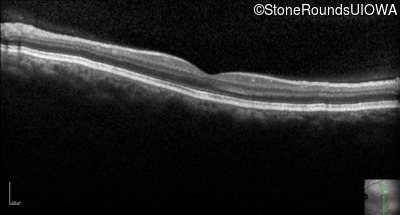

Optical Coherence Tomography - Left - 20/160 -1

Exemplar / OCT Stack